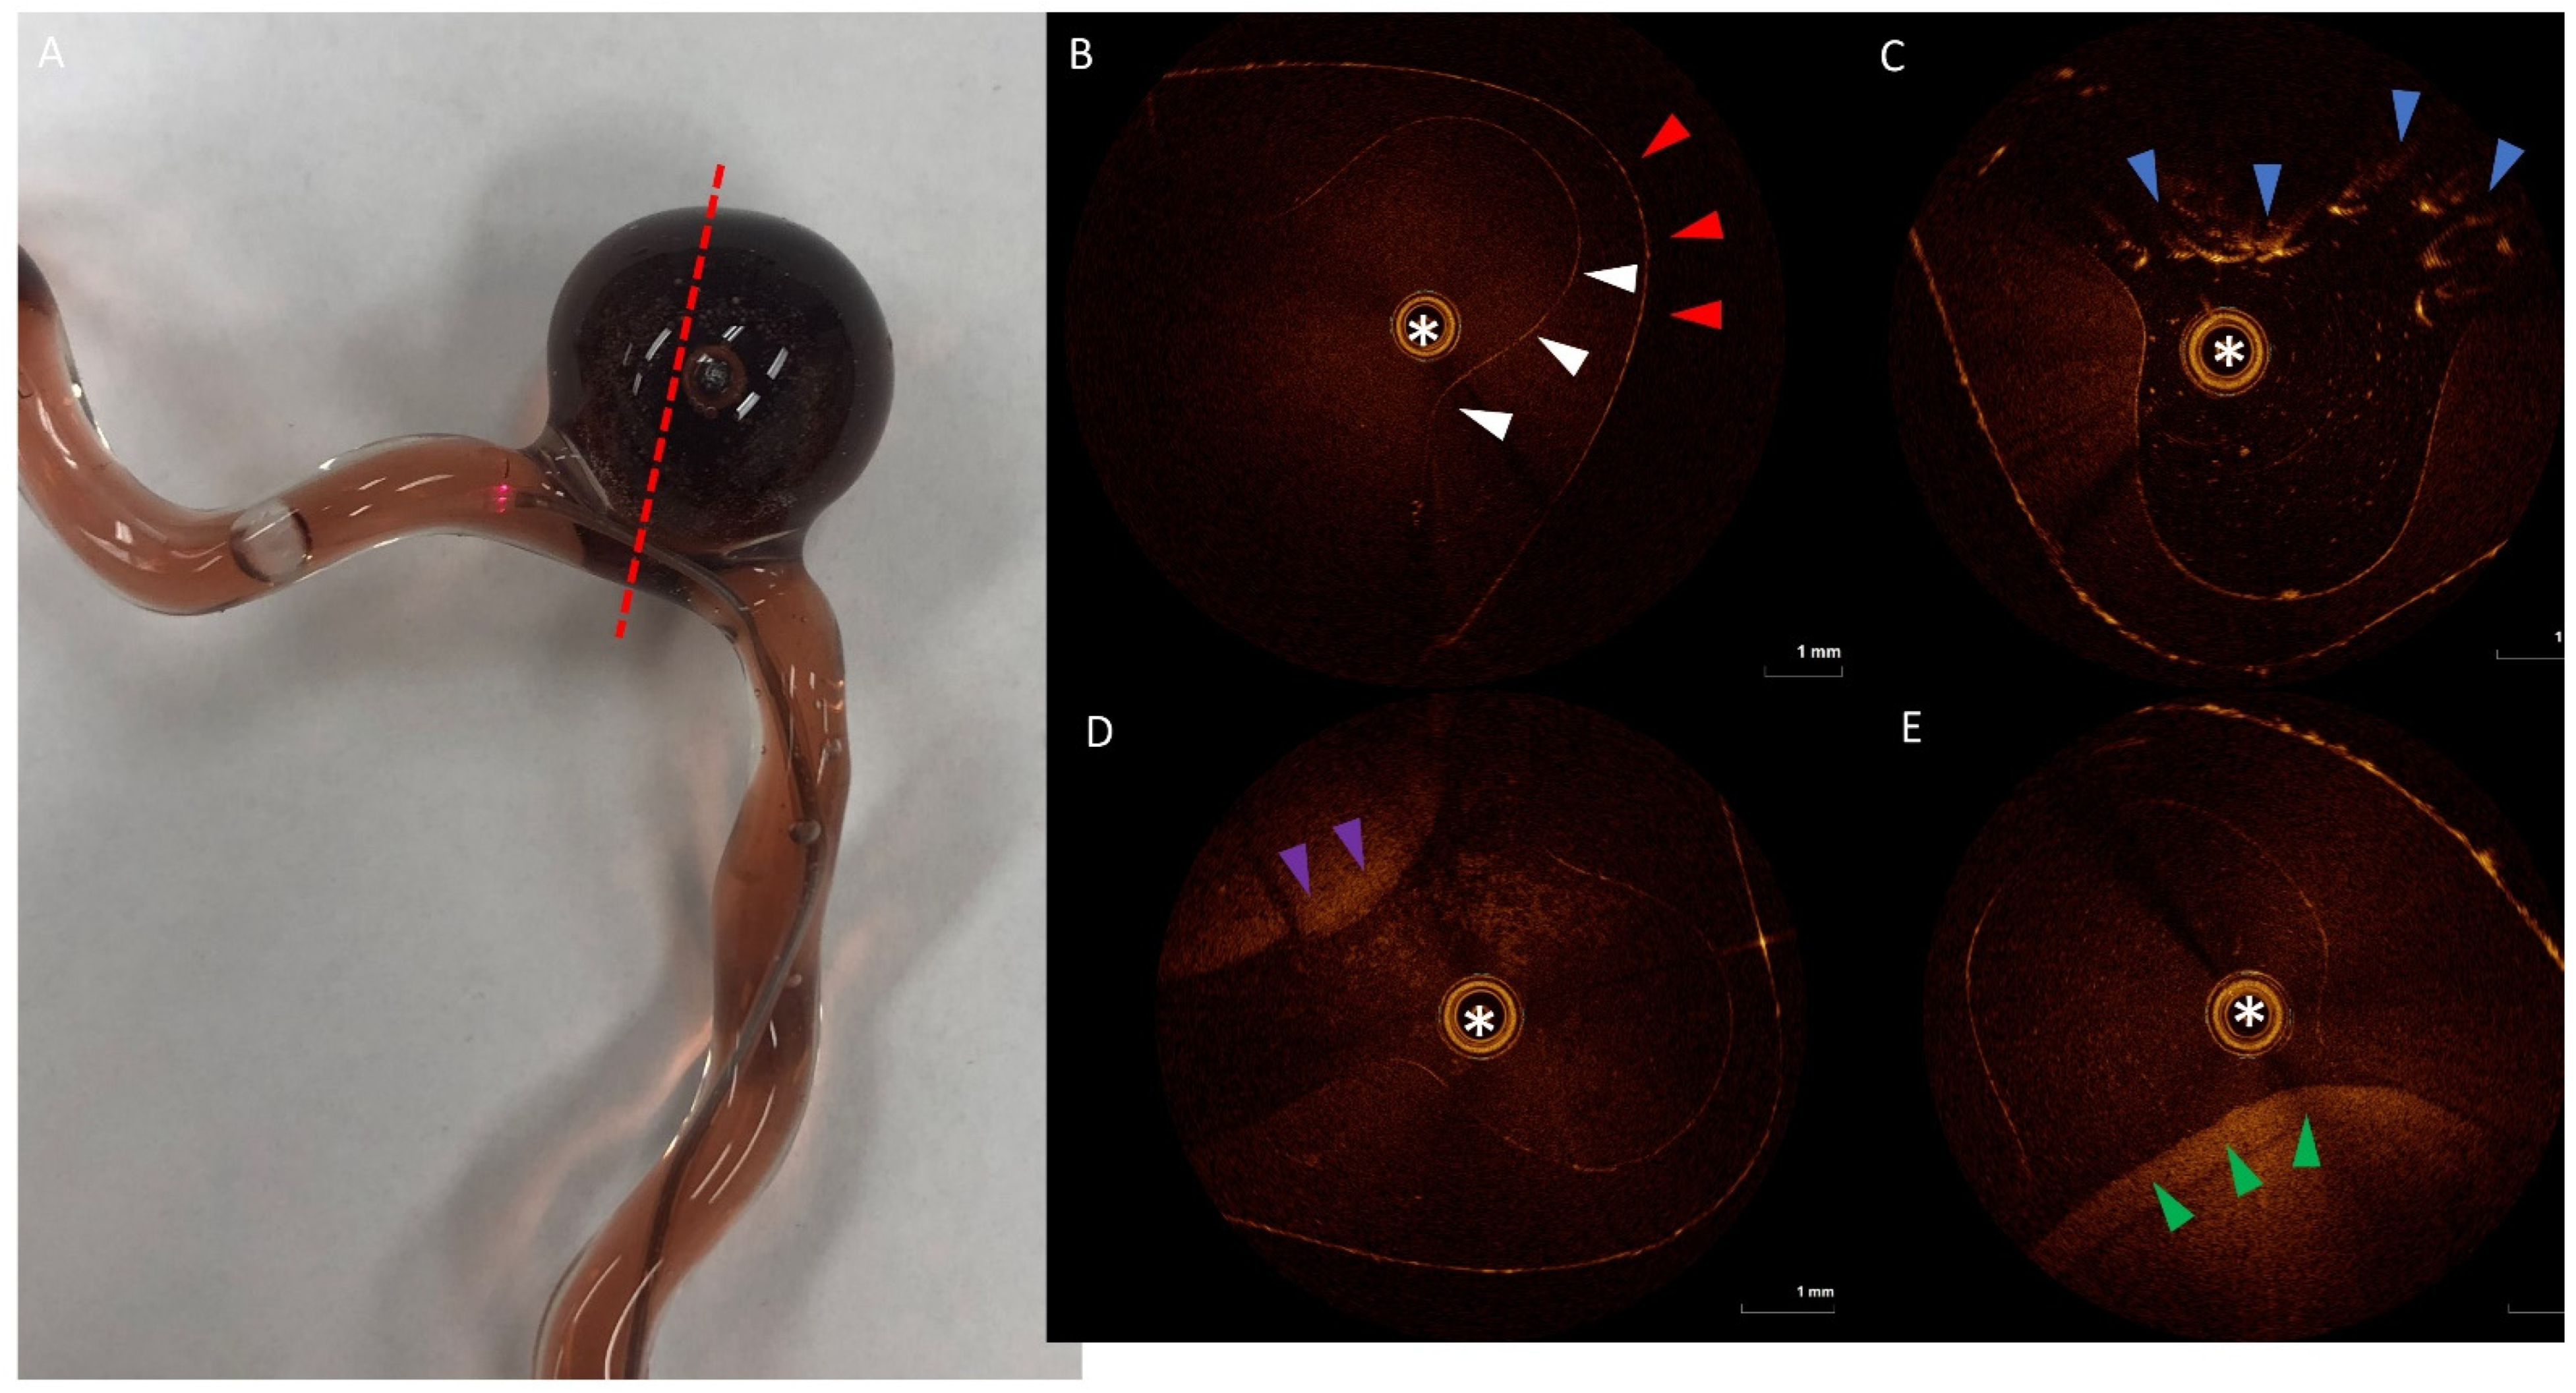

2.1. 3D Model

5.3. 3D Model Testing with OCT